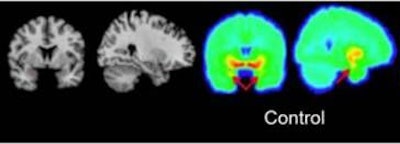

The study included 31 healthy controls and 26 medication-free patients with MDD who received a PET scan using C-11 DASB. The MDD subjects then received eight weeks of standardized therapy with escitalopram.

Ananth and colleagues found a significant difference in amygdala binding, with medication-free patients showing 11% less amygdala binding than the controls. They suggested that 5-HTT amygdala binding should be studied further as a possible biomarker for remission after treatment with escitalopram.